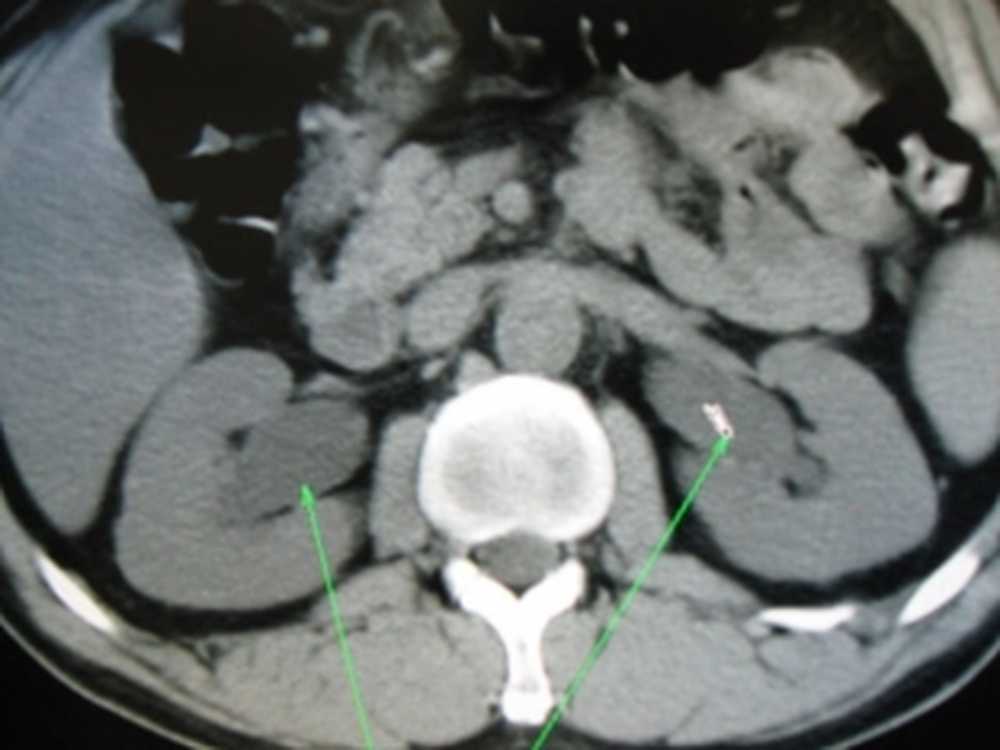

КТ ретроперитонеального фиброза: Изображения и диагностика

Раздел: Мудрость в деталях